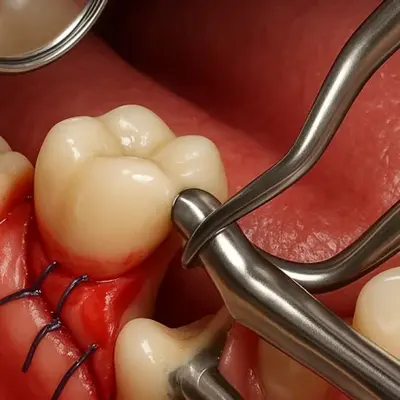

نمای جراحی لثه و خارجسازی دندان عفونی با ابزار دندانپزشکی

برداشتن عفونت دندان در جراحی لثه

ترمیم لثه پس از جراحی دندان با بخیه